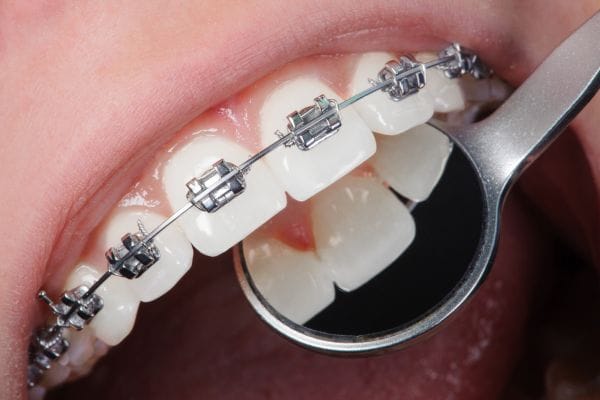

3. Instalación de brackets

Con el plan de tratamiento claro, llega el momento de la instalación de los brackets. Este procedimiento, aunque sencillo, requiere precisión. Primero, el ortodoncista limpia a fondo la superficie de los dientes para asegurar una correcta adhesión. Luego, aplica un adhesivo dental especial y coloca los brackets en cada diente. A continuación, se conecta un arco metálico a los brackets, que será el responsable de aplicar la presión necesaria para mover los dientes a la posición deseada.

Durante este proceso, se ajusta la tensión del arco metálico para asegurar que los dientes se muevan gradualmente. El procedimiento completo puede durar entre una y dos horas, dependiendo de la complejidad del caso.

Después de la instalación de los brackets, el tratamiento no termina. El ortodoncista programará visitas periódicas, generalmente cada cuatro a seis semanas, para ajustar el arco metálico. Estos ajustes son necesarios para asegurar que los dientes continúen moviéndose correctamente.